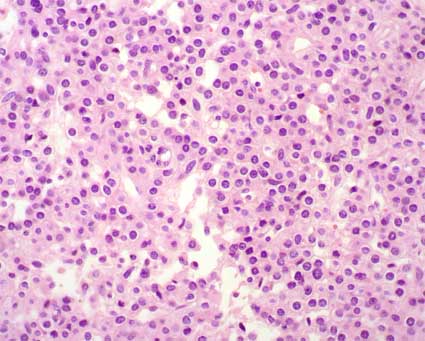

Figura 29. Tumor de céluas yuxtaglomerulares. Hay una disposición sólida de células con limites bien definidos, núcleos centrales, redondos, homogéneos, sin o con muy escasas mitósis. En algunas áreas hay disposición en nidos de las células tumorales, algo similar a carcinoides. (H&E, X400).

Figura 30. En este caso hay disposición menos densa de las células y un patrón algo hemangiopericitoide. (H&E, X400).